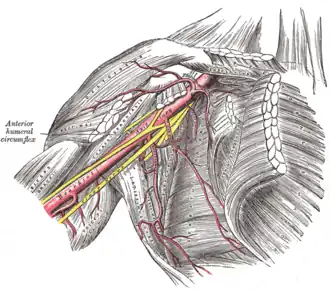

The axillary artery and its branches.

The axillary artery and its branches. -